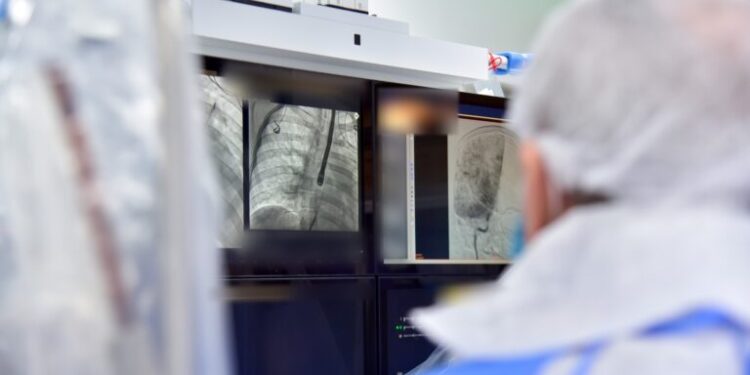

Me anë të një postimi në Facebook të ShSKUK-së bëhet e ditur se këto procedura u kryen për herë të parë në Kosovë, nga një ekip mjekësor vendor i përbërë nga Dr. Daut Gorani, Dr. Denis Zijabegu dhe Dr. Aurora Bakalli, nën mbikëqyrjen e profesorit italian, Prof. Dr. Eustahio Oracio.

“Me suksesin e këtyre procedurave, trajtimi i sëmundjeve strukturale të zemrës tashmë do të jetë i mundur në QKUK, duke përmirësuar qasjen dhe kujdesin për pacientët me këto patologji. Kjo ishte seanca e dytë, ndërsa në seancën e parë u kryen gjithashtu 4 procedura të suksesshme, duke çuar numrin total të pacientëve të trajtuar me defekte të septumit interatrial në 11”.

“Ky është një hap i rëndësishëm për zhvillimin e kardiologjisë publike në Kosovë, drejt shërbimeve të avancuara mjekësore brenda vendit”, thuhet tutje në njoftim.